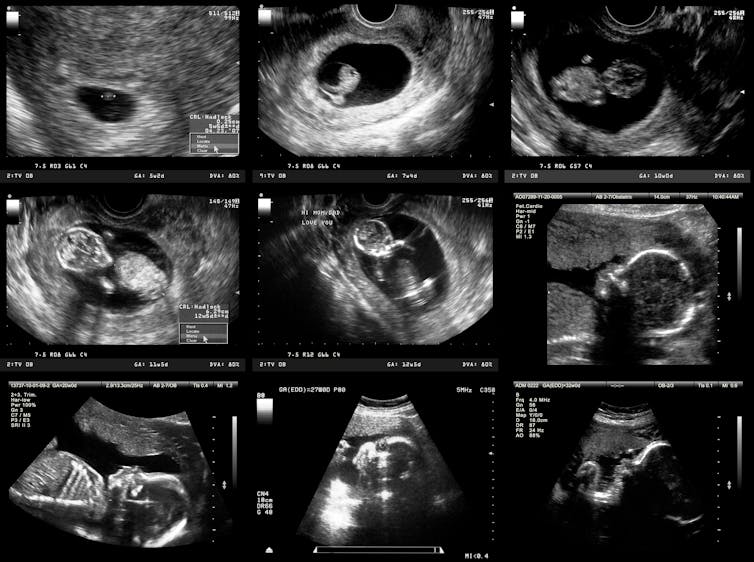

Scott Gilbert, the Howard A. Schneiderman Professor of Biology emeritus at Swarthmore College, is the author of the standard textbook of developmental biology. He has identified as many as five developmental stages that, from a biological perspective, are all plausible beginning points for human life. Biology, as science knows it now, can tell these stages apart, but cannot determine at which one of these stages life begins.

The second plausible stage is called gastrulation, which happens about two weeks after fertilization. At that point, the embryo loses the ability to form identical twins – or triplets or more. The embryo therefore becomes a biological individual but not necessarily a human individual.

The third possible stage is at 24 to 27 weeks of pregnancy, when the characteristic human-specific brain-wave pattern emerges in the fetus’s brain. Disappearance of this pattern is part of the legal standard for human death; by symmetry, perhaps its appearance could be taken to mark the beginning of human life.

The fourth possible stage, which is the one endorsed in the Roe v. Wade decision legalizing abortion in the United States, is viability, when a fetus typically becomes viable outside the uterus with the help of available medical technology. With the technology that we have today, that stage is reached at about 24 weeks.

The final possibility is birth itself.